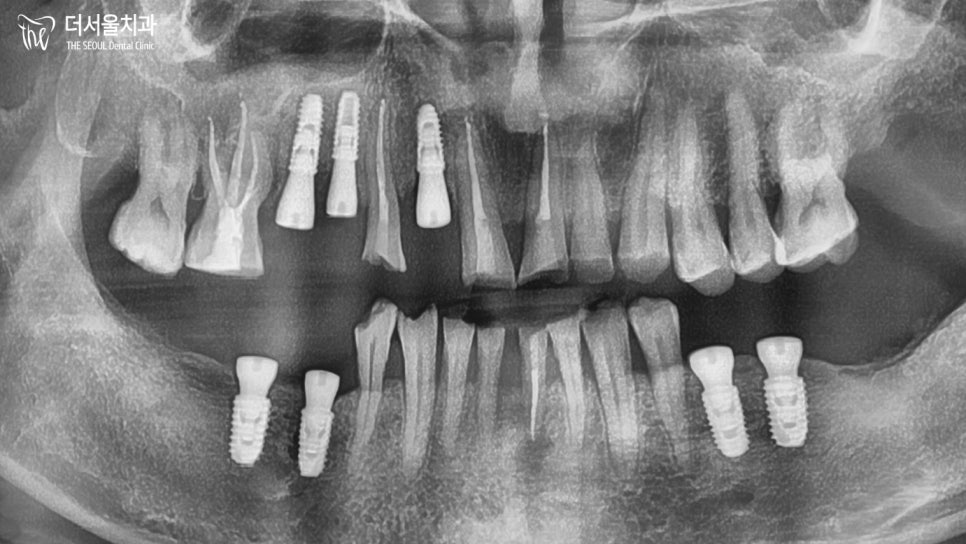

수술 전 모의 시술 프로그램을

시행했습니다.

남아있는 뼈의 상태를 확인하고

그 깊이와 폭, 밀도, 혈관 및 신경 등

문제가 될만한 구조가 없는지

살펴보며 가상으로 픽스처를

식립하여 크라운도 세팅해 보았습니다.

그리고 위아래 맞물리는 점까지

확인한 다음, 이에 맞는 가이드를

만들어서 실제 수술에 들어갔습니다.

통증은 줄이고 빠른 시술이 가능한

네비게이션 가이드 시술을 통해

7개의 임플란트를 안전하게

식립해 드렸습니다.

이를 확인할 수 있는 파노라마를 보면

근관충전이 뿌리끝까지 제대로

되어 있는 것을 볼 수 있습니다.ㅎㅎ

이후, 근관충전한 곳은 증상이 없는지

인공치근은 뼈와 잘 융합이 되었는지

확인한 다음 크라운 을 수복해 드렸습니다.